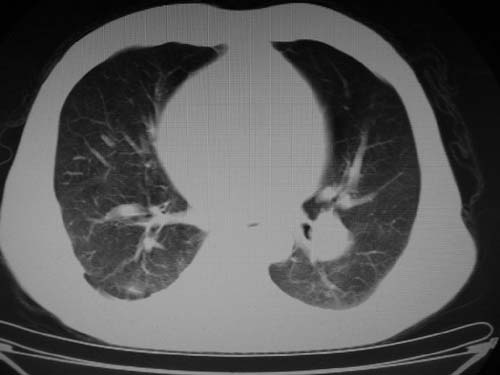

标题: CT17069:M80Y,请战友们看看像啥 [打印本页]

标题: CT17069:M80Y,请战友们看看像啥

男,80岁

肺a高压征[左肺a狭窄?];肺,胸膜tb

右肺上叶结核;左肺门占位?建议增强扫描.

左下肺静脉扩张,原因?建议cta

左肺动脉异常增粗,建议增强。

1)考虑肺动脉狭窄。2)右肺上叶继发性肺结核。3)右侧胸膜增厚、钙化,左侧胸膜反应。

肺动脉瘤。建议先行ct增强扫描

左肺动脉异常增粗,考虑肺动脉狭窄可能。

右肺上叶继发性肺结核。

右侧胸膜增厚、钙化,左侧胸膜反应。

左肺动脉异常增粗,建议ct增强,排除肺门肿瘤

右侧胸膜增厚、钙化,左侧胸膜反应

双肺陈旧性病变,左肺动脉高压.

1)考虑左肺动脉瘤可能性大,建议增强。2)右肺上叶继发性肺结核。3)右侧胸膜增厚、钙化,左侧胸膜反应。

肺动脉段突出,左右肺门不等大,左肺门明显增大,肺动脉干及左肺动脉明显增宽,考虑先天性肺动脉狭窄瓣膜狭窄型。

)考虑肺动脉扩张,右心室增大,主动脉弓段正常位弓后段明显变小(不会是动脉导客未闭吧,不知患者有何症状病史)0。2)右肺上叶继发性肺结核。3)右侧胸膜增厚、钙化,左侧胸膜反应。

右肺上叶尖段结核;左肺下叶占位?建议增强扫描。右侧胸膜增厚;右肺局限性肺气肿。

结合患者年龄,不除外左下肺扩张性动脉瘤,建议胸透是否有扩张性博动,以便确诊。

肺动脉高压,左肺动脉瘤样扩张。

肺a高压